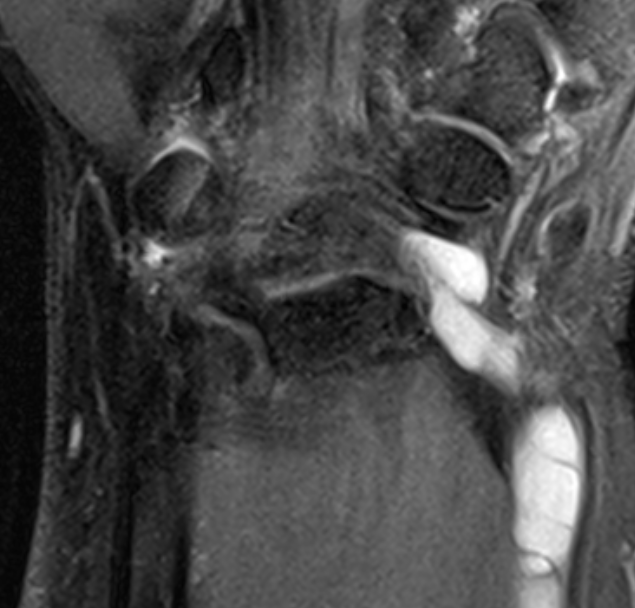

Volar ganglion